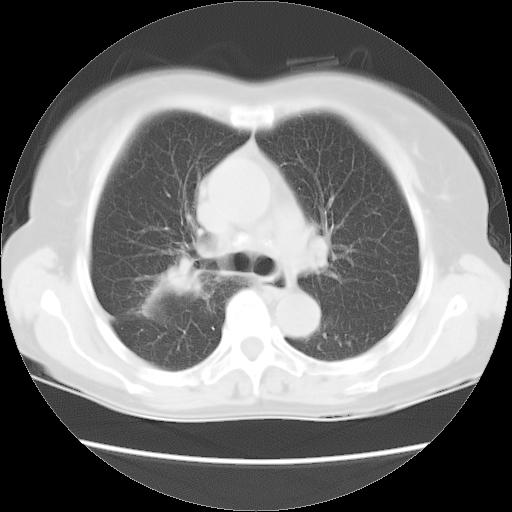

以下是引用夏季在2007-9-18 11:00:00的发言:[br]1。右肺肿块,周围有短毛刺,肺门侧有血管与其相连,胸壁侧有胸膜凹陷征,考虑周围性肺癌 2。左侧甲状腺软组织肿块,内有高密度钙化灶,考虑左侧甲状腺腺瘤。

以下是引用卜一在2007-9-18 14:41:00的发言:[br]右肺肿块:毛刺+胸膜凹陷征+供血血管+浅分叶+强化。支持:周围性肺癌 !另:左侧甲状腺腺瘤!